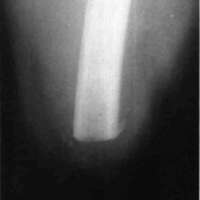

In July, 1983, he was readmitted to IRM-NYU and started on gait training with an AK prosthesis with a semi-suction socket, hip joint and pelvic belt, polycentric knee joint (Lang) and SACH foot (Fig. 1). During the course of his rehabilitation training, he began complaining of pain at the distal stump. The socket was adjusted numerous times by alternately relieving painful areas distally and placing padding above these areas, but with little success. Subsequently, x-rays taken of the stump revealed a small amount of soft tissue calcification distally with a small spur at the posterior lateral side of the femur (Fig. 2). The patient was started on anti-inflammatory agents which provided a moderate amount of pain relief. However, he still had difficulty ambulating secondary to stump pain.

Figure 3: